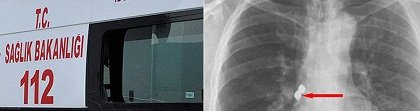

Afyonkarahisar’ın Emirdağ ilçesinde, bir kişinin diş tedavisi sırasında soluk borusuna kaçan iki implant başarıyla çıkarıldı.

Belçika’da yaşayan 56 yaşındaki Emirdağlı gurbetçi Demet Kaplan, geldiği Emirdağ ilçesinde diş tedavisi için bir kliniğe gitti. Operasyon sırasında birbirine yapışık olan 2 implant hastanın dişinden düştü.

Kaplan, yutkununca implantlar soluk borusuna kaçarak burayı tıkadı. Nefes almakta zorlanan Kaplan, Emirdağ Devlet Hastanesinde yapılan ilk müdahalenin ardından Afyonkarahisar’da başka bir hastaneye sevk edildi.

Kaplan’ın akciğer girişinden implantlar başarıyla çıkarıldı.